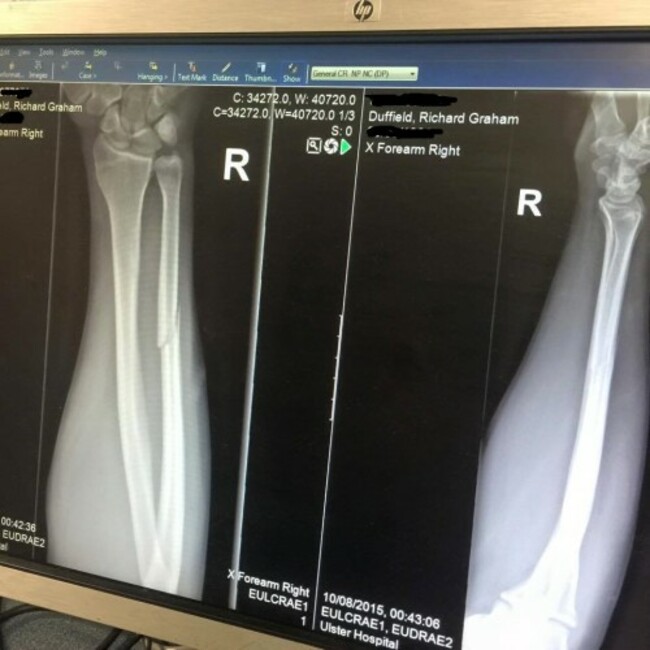

In the fourth quarter, while making yet another tackle, the 33-year old suffered a broken bone on his right arm, this time below the elbow.